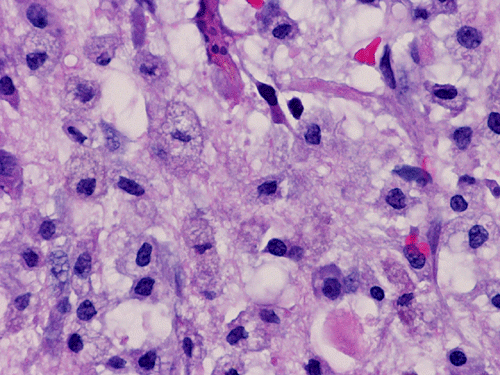

He was admitted again. In this admission, he developed left intraparenchymal hemorrhage associated with the enhancing mass, edema, and 0.4 cm left to right midline shift. A craniectomy was performed to evacuate the blood and biopsy the enhancing mass. The followings are representative images from the biopsy material.

Panel A to E are intra-operative cytologic preparation, Panel E to J are frozen section, Panel K to N are permanent sections.